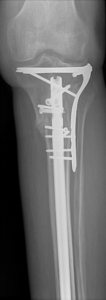

Nonunion and malunion repair related to post-traumatic conditions and/or prior surgery

Acute fracture care of the pelvis and the extremities